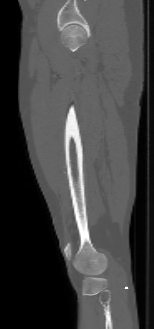

Бедренная кость является наиболее крупной трубчатой костью скелета человека и выполняет основную опорную функцию, обеспечивая прямохождение человека. Головка бедренной кости соединяется с вертлужной впадиной костей таза, образуя тазобедренный сустав, обеспечивающий движения нижней конечности.

КТ предусматривает использование рентгеновского излучения, которое хорошо поглощается костной тканью. В результате сканирования и последующей цифровой обработки полученных данных получаются подробные снимки в различных плоскостях, а также трехмерные изображения бедренной кости и тазобедренных суставов, которые можно увеличить и повернуть в разные стороны.

Снимки высокого разрешения позволяют выявить минимальные изменения в костных структурах и окружающих тканях. Мультиспиральная КТ может применяться в экстренных ситуациях для диагностики травматических повреждений бедренной кости и тазобедренных суставов, в частности, при переломах шейки бедра. Кроме того, исследование незаменимо при планировании оперативного вмешательства, а также в послеоперационном периоде для оценки успешности проведенной операции и для отслеживания процесса восстановления.

КТ бедренной кости помогает выявить воспалительные изменения, очаги деструкции костной ткани, доброкачественные и злокачественные новообразования. При подозрении на опухолевый процесс дополнительно применяется контрастное усиление. Для этого пациенту внутривенно вводится контрастный препарат на основе йода, который в большей степени, чем окружающие ткани, поглощает рентгеновские лучи. Поэтому при попадании в опухолевые очаги он обеспечивает их яркую визуализацию на снимках КТ. Методика контрастирования помогает обнаружить опухоли минимальных размеров, определить точные границы опухолевого очага, степень его прорастания в окружающие ткани, эта информация необходима врачу для назначения эффективной тактики лечения.